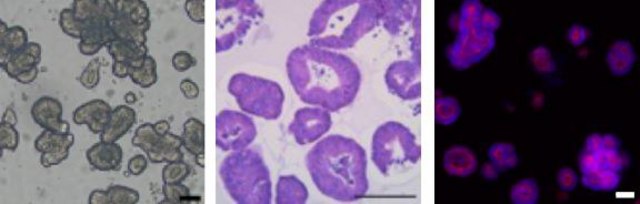

Colorectal cancer accounts for roughly 10% of all cancer cases worldwide with more than half of all patients with CRC developing metastatic disease leading to death. Recently tissue derived organoids have emerged as a more predictive 3 dimensional cell culture model of disease. 3D organoid cultures conserve the original genetic and phenotypic characteristics of the primary tissue allowing for their application in many research fields included drug development, personalized medicine and potential therapeutics. In vitro cultured tumor organoids have also been shown to predict patient response to chemotherapeutics. PDOs derived from colorectal cancer (CRC organoids) have been used for cell modeling and to investigate the function of cancer related driver gene mutations including APC, TP53, KRAS, BRAF, PIK3CA etc.

3dGRO® Human CRC Organoids are offered in a ready-to-assay format intended to simplify the organoid cell culture workflow. A single vial of organoids is enough to directly thaw and seed into a 96-well plate without cell expansion for drug screening applications. The organoids are manufactured using Cellesce’s patented technology which enables the robust growth and expansion of patient-derived organoids (PDOs). Cellesce’s technology minimizes manual handling time to maximize reproducibility in order to position organoid cell models as a cost effective and accurate tool in early-stage drug discovery. The organoid biobank includes tumor derived colorectal cancer PDOs from a range of genetic backgrounds, driver gene mutations, tumor sites and cancer stages. These organoid cell lines have been well characterized and are all validated for response against a number of known CRC-targeting agents.

Cell Growth: Organoid expansion after 7 daysMycoplasma: NegativeViral Testing: Negative (HIV-1, HIV-2, HBV, CMV, EBV, HPV)Sterility (Bacteria, Yeast, Fungi): NegativeMutational Profile: APC ∆R1450*A1446Lfs*27, TP53 ∆R248Q, KRAS ∆G12D, PIK3CA ∆E542K, FBXW7 ∆R465C

Ready-to-Assay human colorectal cancer organoids for 3D cell culture applications.